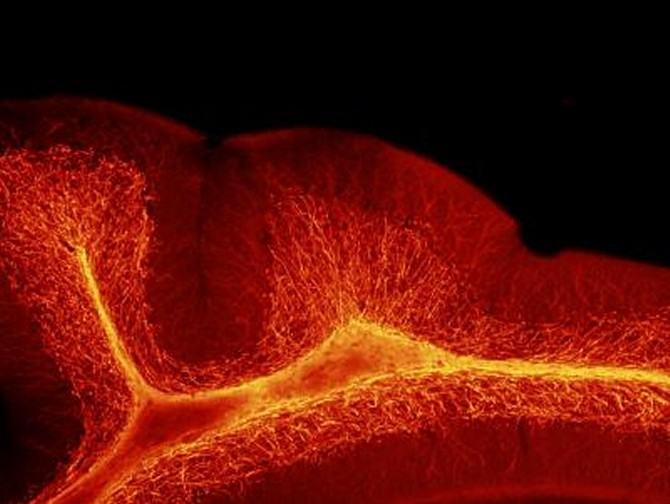

Mielina. (Foto: Children's National Hospital)

“Desde la perspectiva estructural, las anormalidades más pronunciadas aparecieron en la materia blanca del cerebelo”, añade Vacher. “Encontramos un mayor grosor de la mielina, una capa aislante rica en lípidos que protege las fibras nerviosas. Desde la perspectiva del comportamiento, los descendientes masculinos cuyo suministro de ALLO fue reducido de manera abrupta exhibieron un mayor comportamiento repetitivo y déficits de sociabilidad, dos características en los humanos que tienen trastorno del espectro autista”.